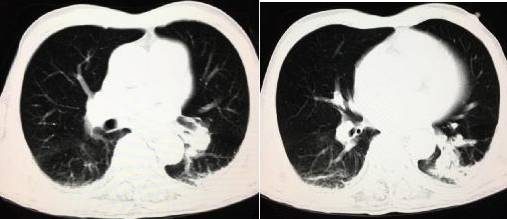

牢记急性肺动脉栓塞的三大征象!

患者,男,61岁,左侧股骨颈骨折术后,胸部CT检查: 医学百科网 | YxBaike.Com

肺窗:

诊断:急性肺动脉栓塞

1、平扫管腔内高密度征:急性肺栓塞的特征性表现,特别是栓塞累及中心肺动脉时该征象更加明显,诊断肺栓塞的总敏感度为 36%,特异度为 99%,在诊断中心肺动脉栓塞时,其敏感度为 66.7%,特异度为 99.1%。